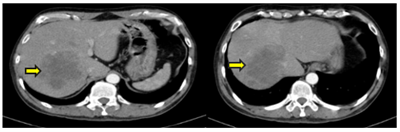

CASE LÂM SÀNG: CHẨN ĐOÁN BỆNH NHÂN MẮC HAI UNG THƯ:  GIST RUỘT NON VÀ UNG THƯ TUYẾN GIÁP TẠI TRUNG TÂM Y HỌC HẠT NHÂN VÀ UNG BƯỚU, BỆNH VIỆN BẠCH MAI

U mô đệm đường tiêu hóa (GIST) là bệnh lý hiếm gặp, chiếm 0,1% – 3% các u ác tính đường tiêu hóa với tỷ lệ mắc mới hàng năm từ 10 – 15 ca/triệu dân. Theo GLOBOCAN 2022, ung thư tuyến giáp đứng hàng...